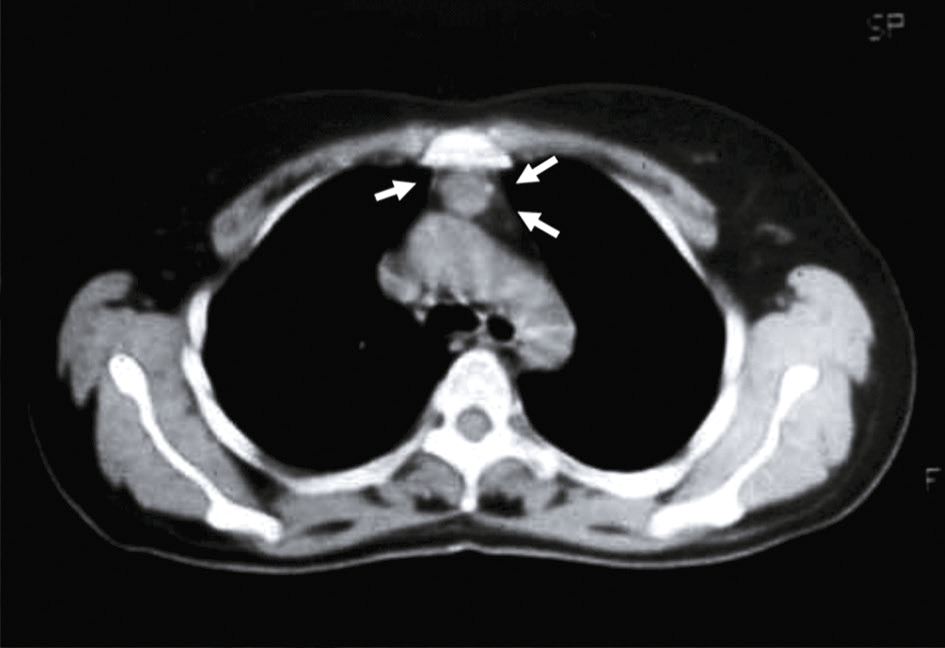

Le scanner thoracique sans injection doit être systématique devant toute suspicion de myasthénie, afin d’explorer la loge thymique à la recherche d’une hyperplasie thymique ou d’un thymome (bénin ou malin) (figure 9.3).

Scanner thoracique. Thymus hyperplasique résiduel.Sur cette coupe axiale de scanner thoracique injecté, on observe une masse tissulaire triangulaire en densité homogène située en avant des gros vaisseaux du médiastin antérieur. Les flèches blanches désignent cette structure bien délimitée, en position rétro-sternale haute. Son rehaussement modéré et sa symétrie par rapport aux lignes médianes suggèrent un thymus hyperplasique résiduel, souvent retrouvé chez l’adulte jeune ou après un stress systémique. Aucun signe d’infiltration des structures vasculaires adjacentes ni de masse compressive n’est observé. L’aspect global oriente vers une hyperplasie thymique bénigne plutôt qu’une pathologie tumorale invasive.

En cas de doute sur un thymome, une injection d’iode est indiquée, mais en dehors d’une poussée, car elle peut aggraver une myasthénie instable.